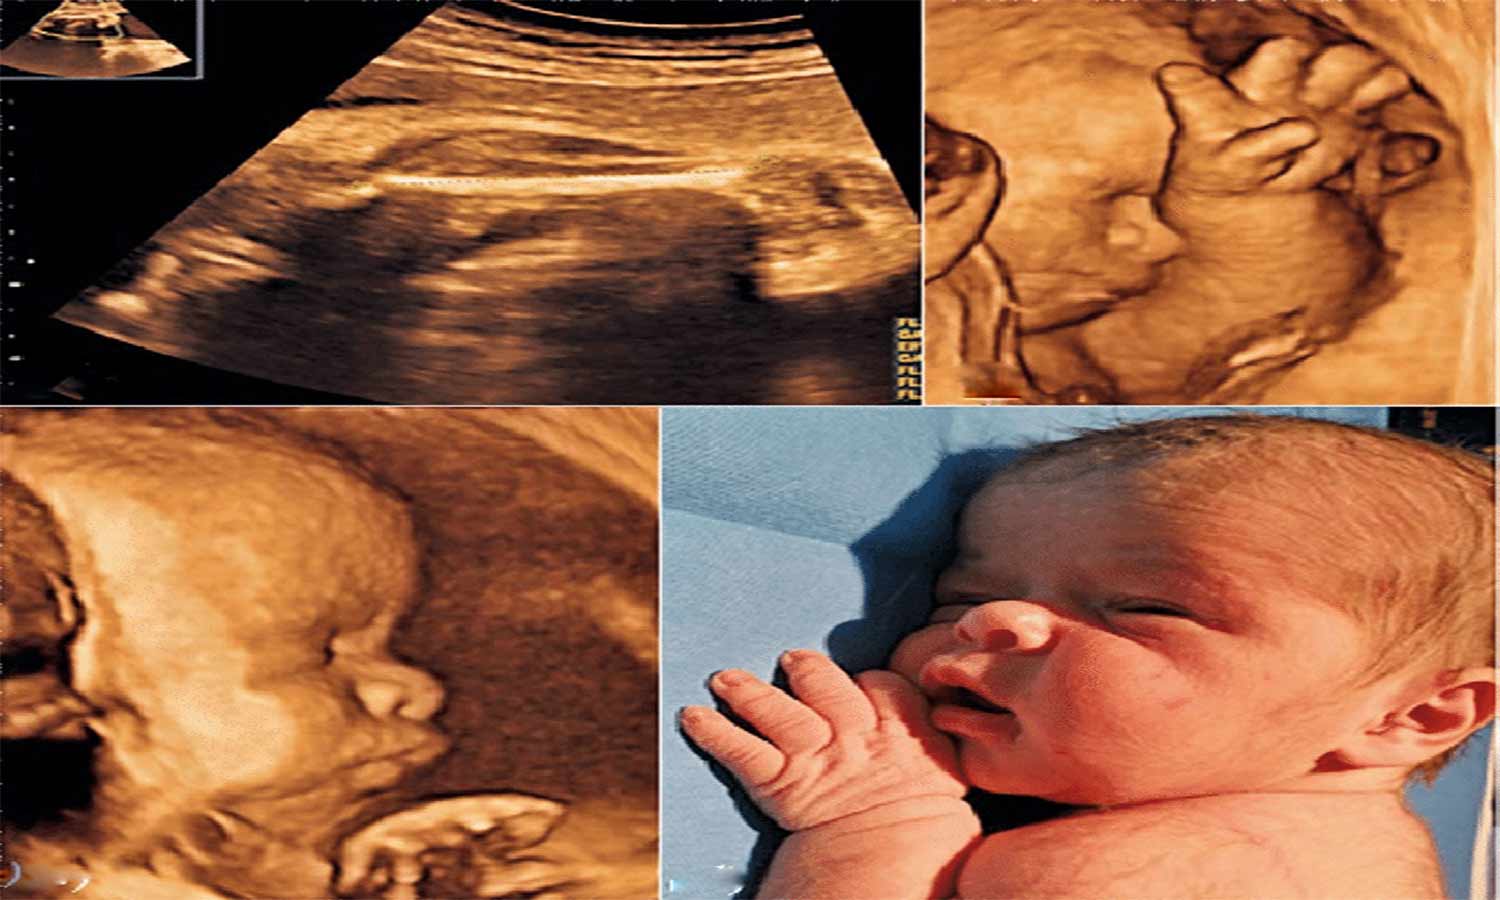

வேலூர் மாங்காய்மண்டி பகுதியை சேர்ந்தவர் கரண் (வயது 25). இவரது மனைவி சிவசக்தி. இவர் மக்கான் பகுதியில் உள்ள சுகாதார நிலையத்துக்கு பிரசவத்துக்காக நேற்று முன்தினம் அழைத்துச் சென்றனர்.

பின்னர் அவரை பென்லேன்ட் மருத்துவமனைக்கு அழைத்துச் சென்றனர். அவருக்கு குழந்தை இறந்து பிறந்தது. இந்த சம்பவம் வேலூரில் பரபரப்பை ஏற்படுத்தியது.